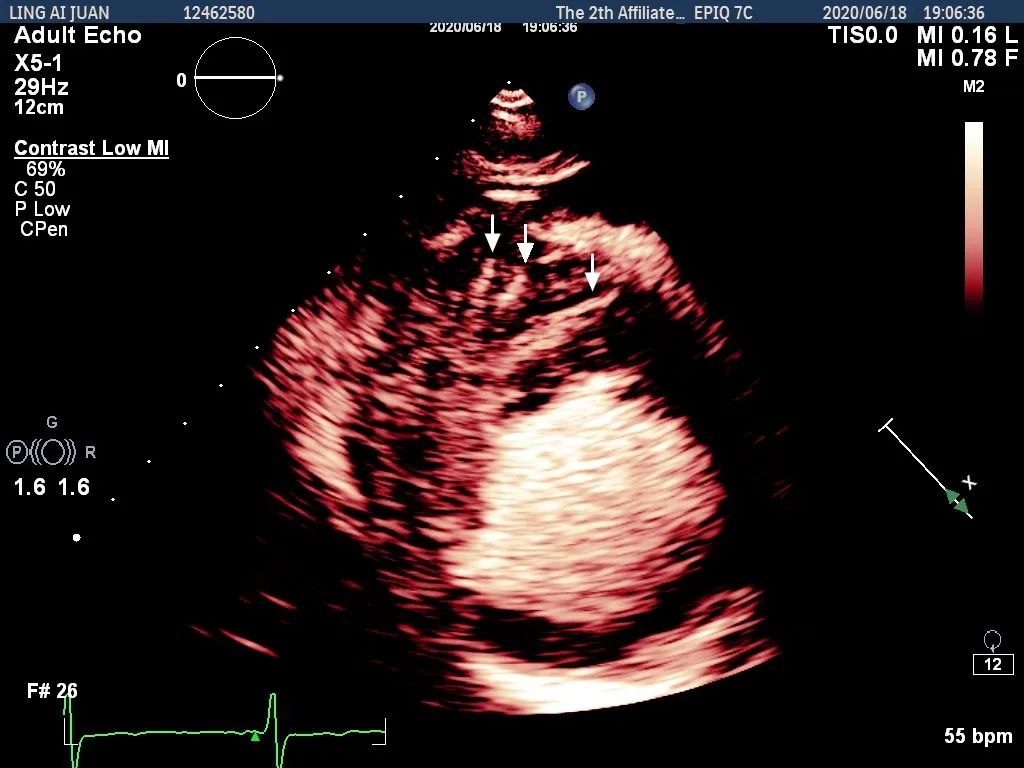

术前心肌超声造影示肥厚室间隔内丰富的穿隔支

Liwen术式成功消融术后心肌造影示“黑洞”效应